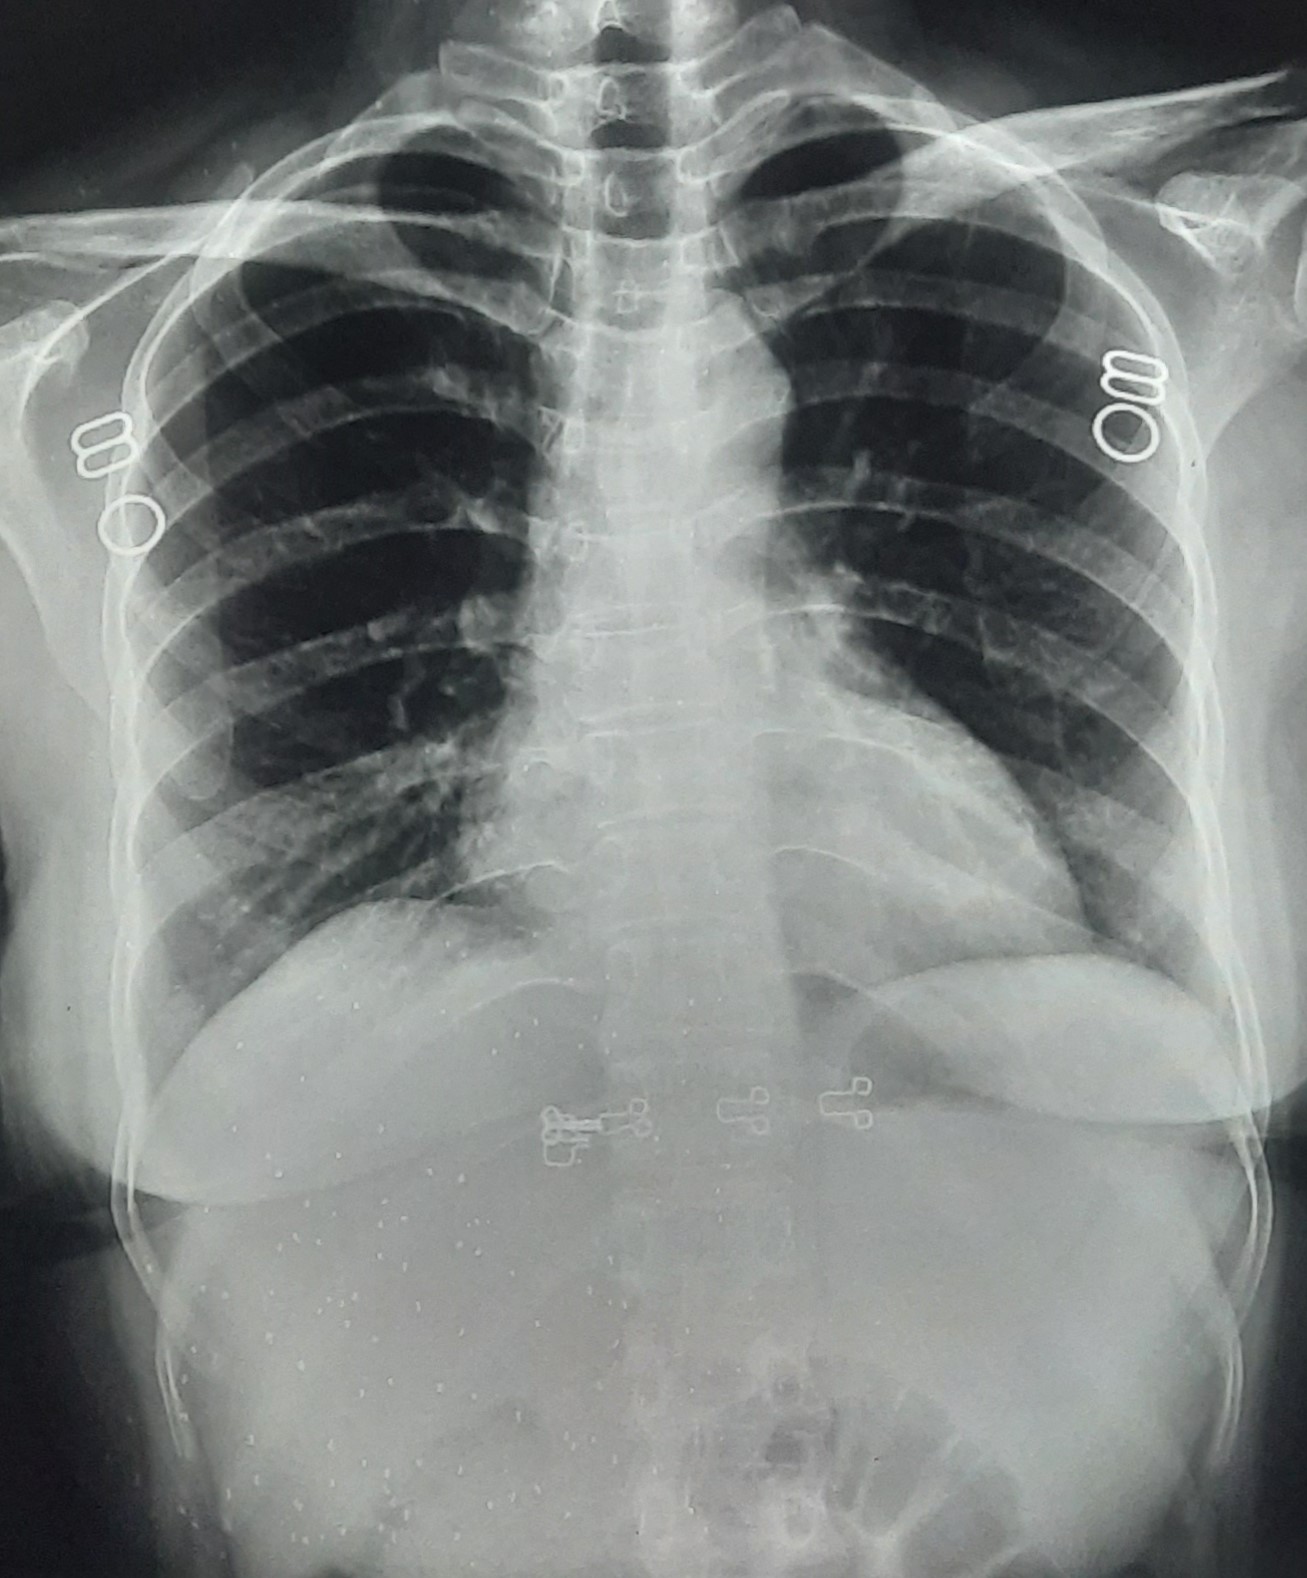

| IGGMC, Nagpur | 29-4158 | IGGMC, Nagpur | Nita Shende | Clinically Diagnosis Tubercular Cervical Lymphatics On ATT 26-Aug-24 (6 Month) |

| Chest X-Ray Image |